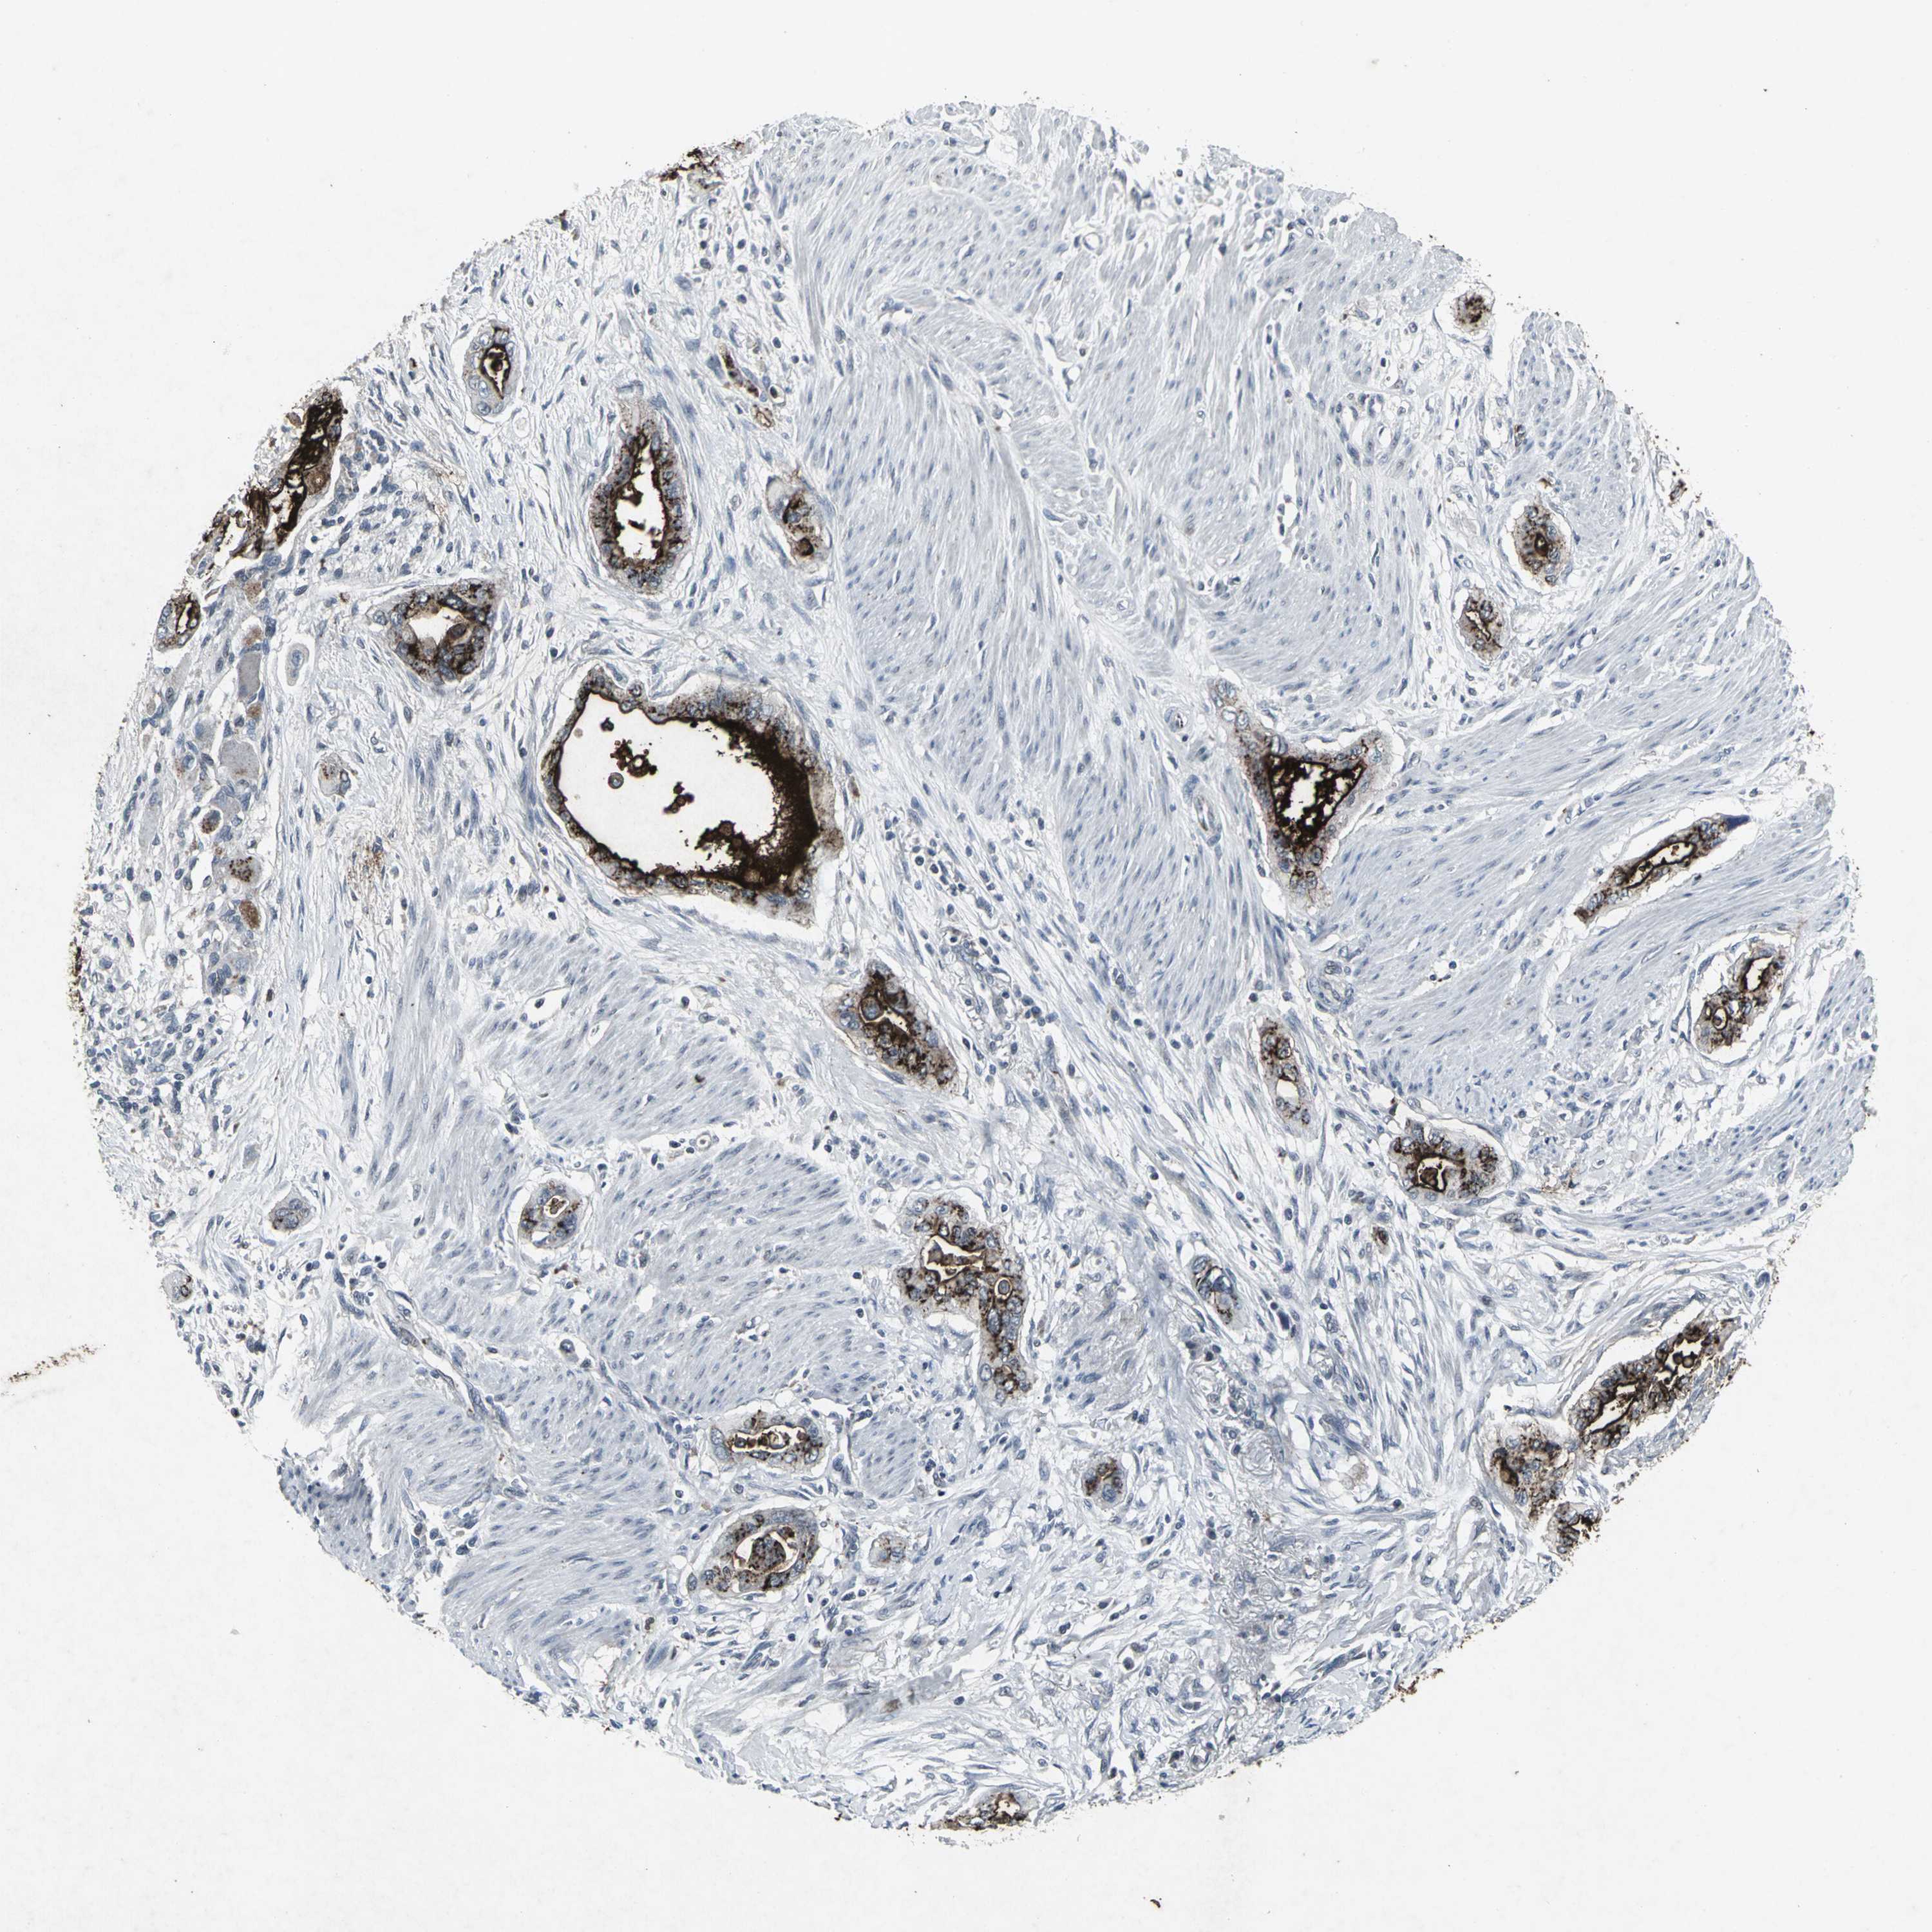

PANCREATIC CANCER - Protein expressioni

A mouse-over function shows sample information and annotation data. Click on an image to view it in a full screen mode. Samples can be filtered based on level of antibody staining by selecting one or several of the following categories: high, medium, low and not detected. The assay and annotation is described here.

Note that samples used for immunohistochemistry by the Human Protein Atlas do not correspond to samples in the TCGA dataset.

Antibody stainingi

Antibody staining in the annotated cell types in the current human tissue is reported as not detected, low, medium, or high, based on conventional immunohistochemistry profiling in selected tissues. This score is based on the combination of the staining intensity and fraction of stained cells.

Each image is clickable and will lead to virtual microscopy that enables deeper exploration of all samples and also displays staining intensity scores, fraction scores and subcellular localization as well as patient and tissue information for each sample.

Antibody HPA066235

Antibody CAB006863

Staining

High

Medium

Low

Not detected

Intensity

Strong

Moderate

Weak

Negative

Quantity

>75%

75%-25%

<25%

None

Location

Nuclear

Cytoplasmic/membranous

Cytoplasmic/membranous,nuclear

Adenocarcinoma, NOS

Adenocarcinoma, metastatic, NOS